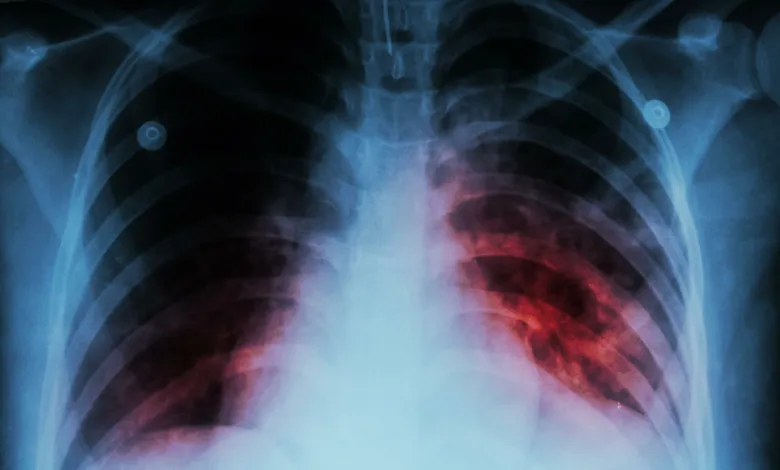

Tuberculosis kills 30 people daily in Ghana

A senior technical officer at the Greater Accra Regional TB Control, Isaac Opoku Asamoah, has said 30 people die daily through tuberculosis (TB) and 125 people contract the disease on a daily basis in Ghana.

He said TB is a silent killer, and adults in most parts of the developing world, including Ghana, are unknowingly exposed to TB bacteria.